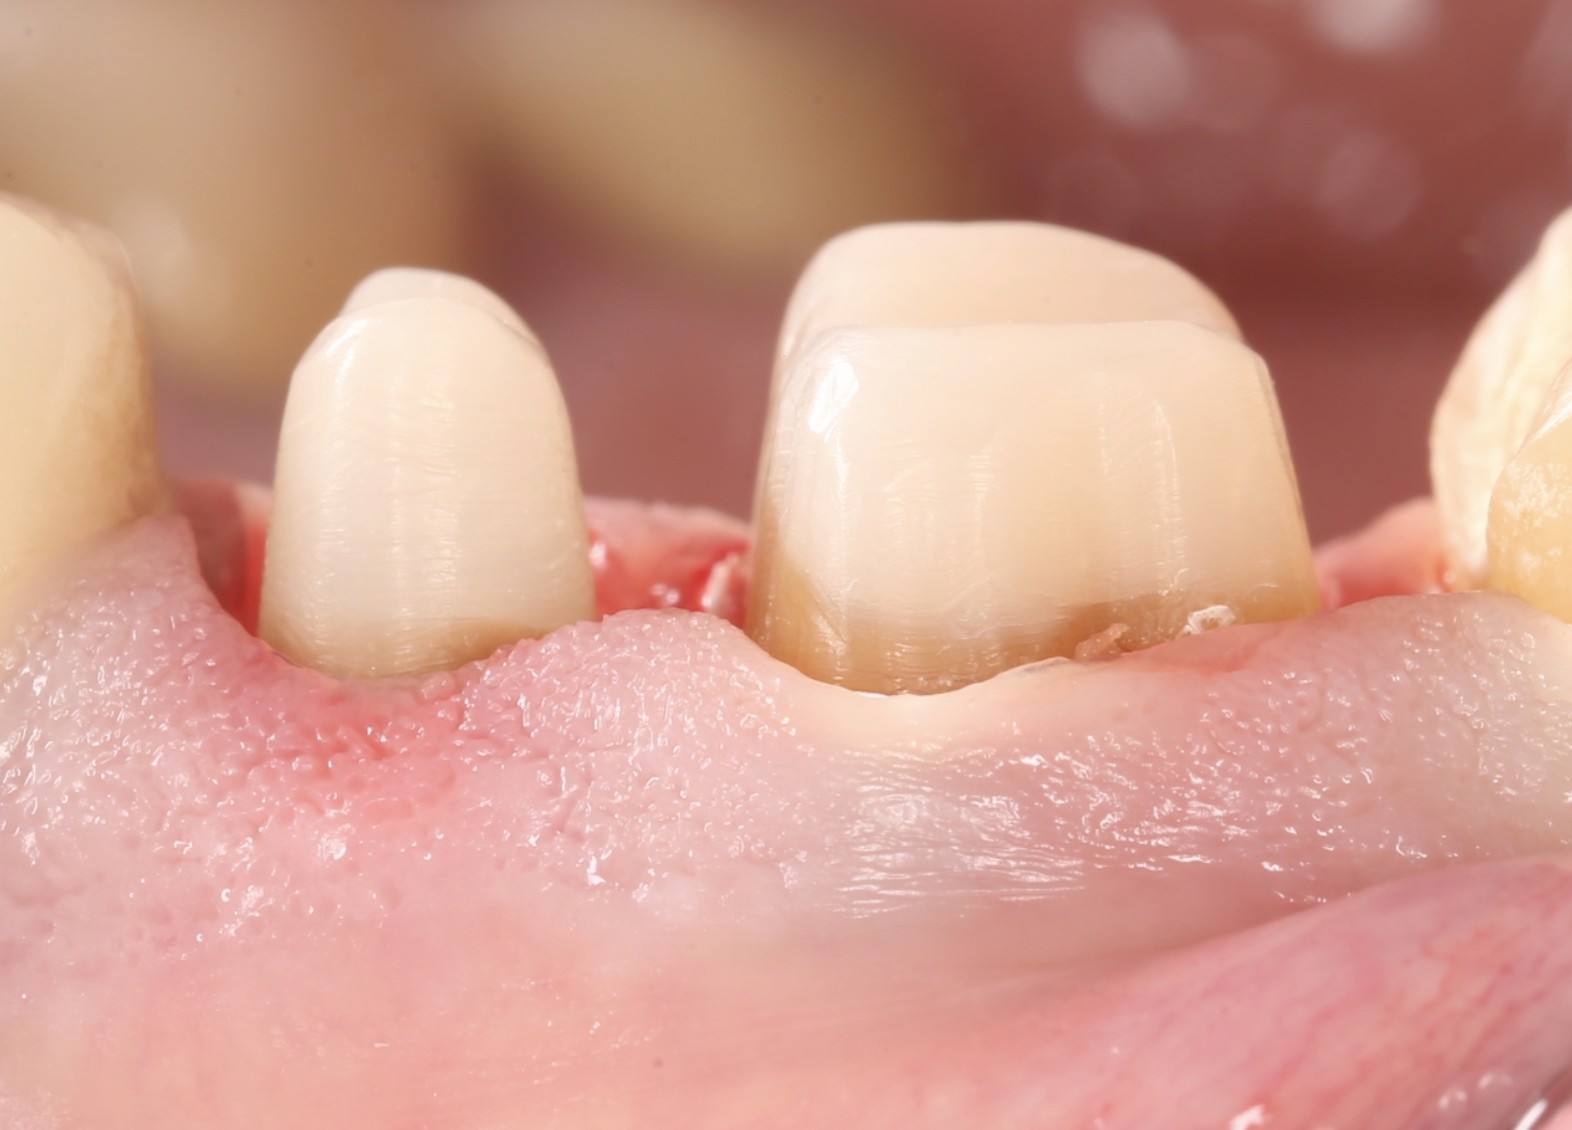

Все про препарування з уступом та без нього

Все про вертикальне препарування та преп з уступом. Чіткі клінічні протоколи

Препарування з уступом та без нього